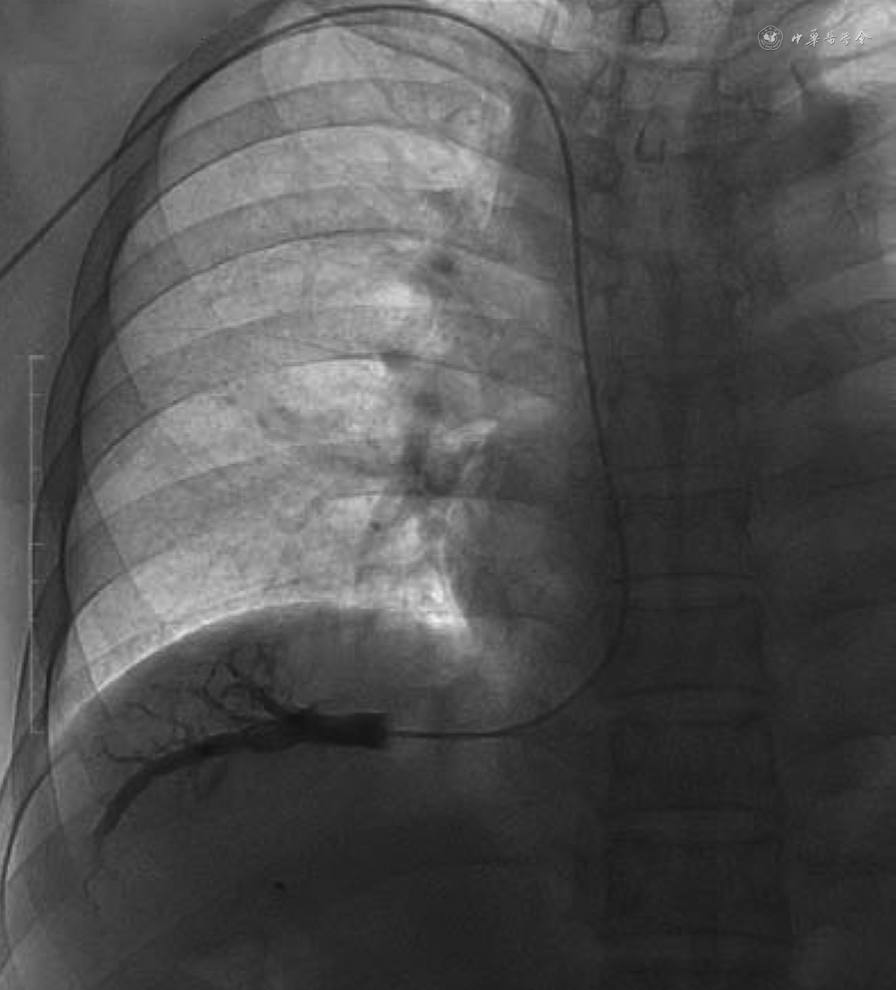

3. 物品准备:(1)标准的检测需要全程记录压力数值的变化,确保测压的连续性和稳定性,因此需要准备能持续记录测压过程的记录仪。压力连续记录需要纸质版或电子版全程记录整个测压过程(图1);(2)建议使用记录静脉压力的量程,一般选择0~50 mmHg,且两条相邻刻度的网格相差1~2 mmHg。如使用动脉压力的量程,则无法清晰地在图纸上记录较小的压力改变;(3)记录的走纸速度建议1~5 mm/s;(4)记录图纸的网格清晰打印;(5)建议根据记录图纸判读压力。

3. 入路:(1)穿刺入路选择:HVPG的测量通常选取经右侧颈内静脉路径。常规消毒、铺无菌洞巾,局部麻醉,穿刺成功后置入导管鞘,利用导丝将导管经上腔静脉、右心房引入下腔静脉。将造影导管(例如多功能导管、单弯导管或Cobra导管)引入肝静脉分支,先进行肝静脉造影检查,确认拟测压静脉通畅、无狭窄,周边未见明显的静脉-静脉侧支分流,则可选择该肝静脉为测压血管(否则必须更换其他肝静脉)。再引入导丝,退出导管并经导丝引入球囊导管至肝静脉入口处。退出导丝,回抽见血后注入生理盐水排净球囊导管内血液及对比剂,连接球囊导管和压力转换器连接管,注意避免产生气泡。经前臂静脉入路(肘正中静脉、贵要静脉、腋静脉等)行HVPG检测已经被证实可安全可靠地完成,无严重不良并发症,并且具有增加患者舒适性、减少放射暴露等优势,建议具备一定检测经验的团队开展(图2)。Akira汇报了41例经前臂静脉系统测量HVPG,具有98%检测成功率,以及较短的操作时间(中位操作时间19.1 min)。经前臂静脉系统测量的HVPG数值与白蛋白胆红素评分、Child-Pugh评分、终末期肝病模型评分、Lok指数呈显著正相关,与血小板计数呈显著负相关,表明经前臂静脉系统测量HVPG与门静脉高压程度、肝功能和血清学模型具有很好的相关性[95]。(2)肝静脉分支选择:考虑到肝静脉插管难度及测压准确性,建议首选肝右静脉;当肝右静脉存在狭窄或静脉-静脉侧支分流时,可更换为肝中静脉。